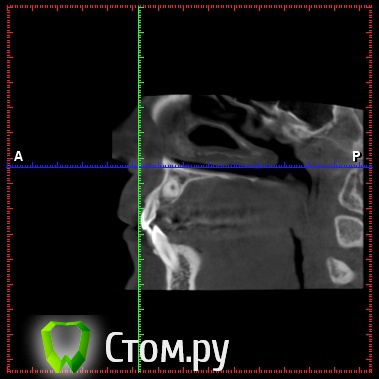

diesel87 Опубликовано 19 декабря, 2013 Поделиться Опубликовано 19 декабря, 2013 Обратилась пациентка, ретенированный 13, располагается горизонтально, брекет систему ставить не хочет, просит удалить этот клык и поставить на его место имплантат, меня интересует вот что, клык то я удалю, что с последующей имплантацией и когда ее провести, просто по кт клык залегает перпендикулярно ось имплантата, прилагаю срезы кт Ссылка на комментарий

Yurij.k Опубликовано 20 декабря, 2013 Поделиться Опубликовано 20 декабря, 2013 (изменено) Небным доступом удалять планируете?Вестибулярно нет смысла идти, большой риск повреждения корней впереди стоящих зубов, и сам зуб расположен небно. Изменено 20 декабря, 2013 пользователем Yurij.k 2 Ссылка на комментарий

diesel87 Опубликовано 21 декабря, 2013 Автор Поделиться Опубликовано 21 декабря, 2013 Небным доступом удалять планируете?Да, небным, лоскут откинуть и коронка сразу под ним, немного косточки убрать, коронку отпилить и затем корень, в оралсерджери красиво такие удаления расписаны и иллюстрированы. Ссылка на комментарий